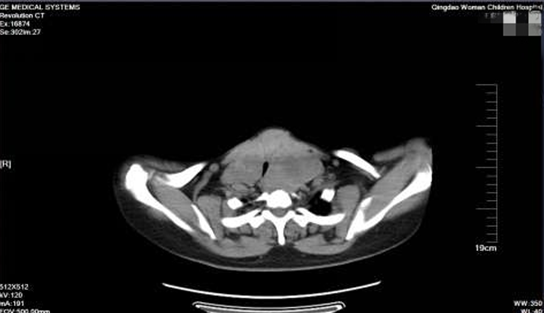

近日,王女士慕名來到青島婦兒醫(yī)院乳腺甲狀腺外科就診,接診醫(yī)生完善檢查后將其收治住院。CT檢查發(fā)現(xiàn)甲狀腺雙側(cè)葉巨大,左葉10*6*4cm,右葉12*8*5cm。上部抵達下頜角,向后可達咽后間隙,患者胸廓入口處氣管局部受壓右偏。